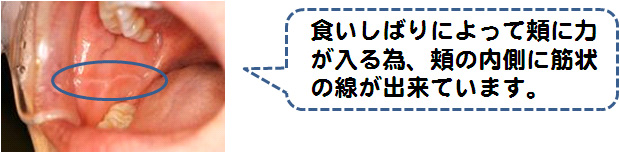

お口の中でも様々な諸症状が診られます!

これらの症状が1つでもあれば口腔外科専門医が居る医院に受診されることをおすすめいたします。又、これらの症状がなくても